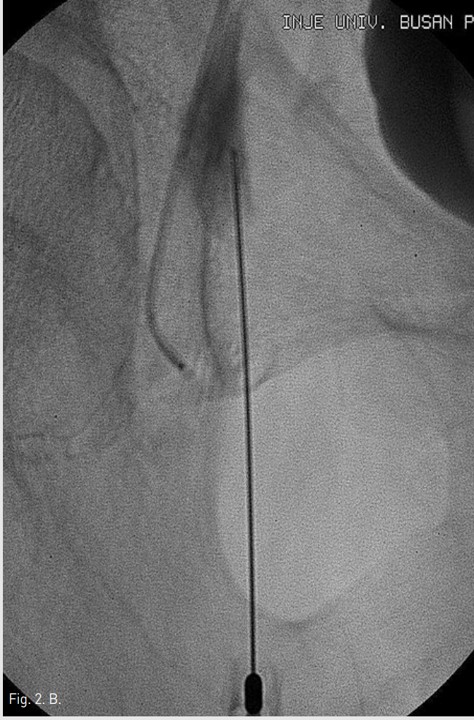

Fig. 2. B

Fig. 2B. Percutaneous glue embolization was tried after blocking the opening of the aneurismal neck with a 5F Cobra catheter, but failed.